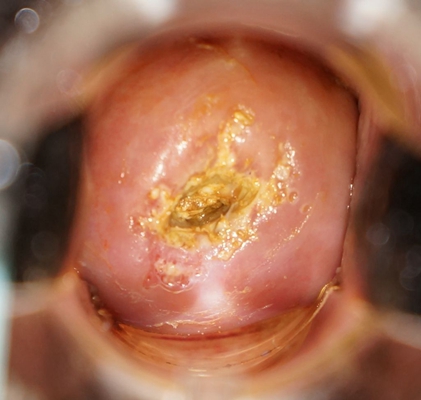

子宮頸癌圖片

宮頸癌

宮頸癌

宮頸癌

宮頸癌

宮頸癌

宮頸癌

宮頸癌

宮頸癌

宮頸癌

宮頸癌

宮頸癌

宮頸癌

宮頸癌

宮頸癌

宮頸癌

宮頸癌

宮頸癌

宮頸癌

宮頸癌

宮頸癌